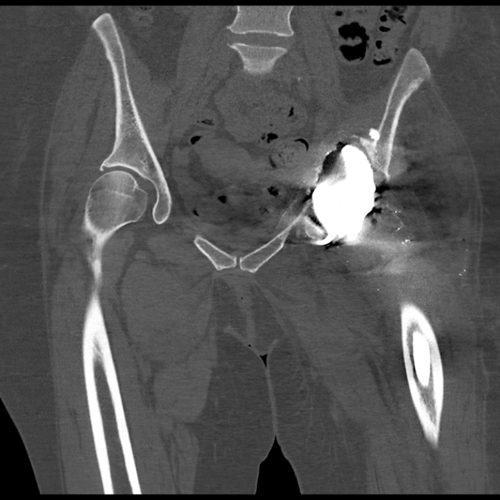

CT scan showing the patient’s pelvis without the acetabular metal work. This was used to make the hemipelvic 3D model seen below.

CT scan demonstrates optimal positioning of the acetabular component

CT scan at 7-months shows no migration of the implant.